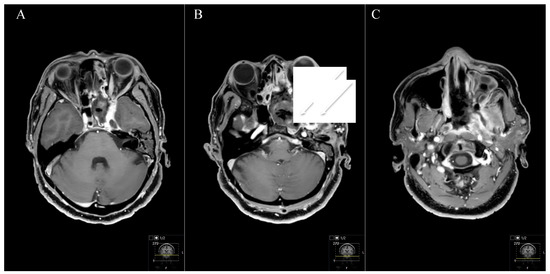

Figure 10. Postoperative outcome and MRI control (see Figure 9) (AC) Postoperative axial T1-weighted gadolinium-enhanced MRI showing a satisfactory STR with small remnants in the maxillary sinus (arrows in (B)). Resection was performed by an endoscopic transnasal approach using the tumor-related widened corridor to the maxillary sinus. The patient recovered very well, the visual impairment recovered subsequently, the abducens nerve palsy and the facial pain during follow-up as well. The trigeminal hypesthesia remained. The patient had follow-up controls without any progress.

Two patients with STR underwent postoperative radiation with an uneventful course and stable disease. The patient with the Type D schwannoma had a transnasal approach with STR (Figure 9 and Figure 10). However, she showed no progress during follow-up. Total adverse event rate requiring surgical intervention during follow-up was 7.7%, with one patient developing a postoperative hydrocephalus during follow-up. The patient received a ventriculoperitoneal-shunt implantation. Surgery-related mortality was 0%.